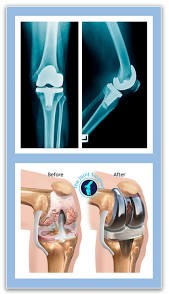

A total knee replacement (TKR) is a surgical procedure that resurfaces damaged knee joint surfaces with metal and plastic components to relieve severe pain and disability, most commonly caused by arthritis. It is typically recommended when other treatments fail to provide adequate relief.

The procedure involves removing damaged bone and cartilage from the thigh bone (femur), shin bone (tibia), and sometimes the kneecap (patella), and replacing them with artificial components. Recovery includes structured physical therapy to restore mobility and strength.

- Resurfacing: The surgeon reshapes the ends of the femur and tibia and resurfaces the underside of the patella using durable metal and plastic implants.

- Components: The artificial knee typically includes a metal femoral component, a metal tibial plate, and a plastic spacer between them, often with a plastic “button” for the kneecap.